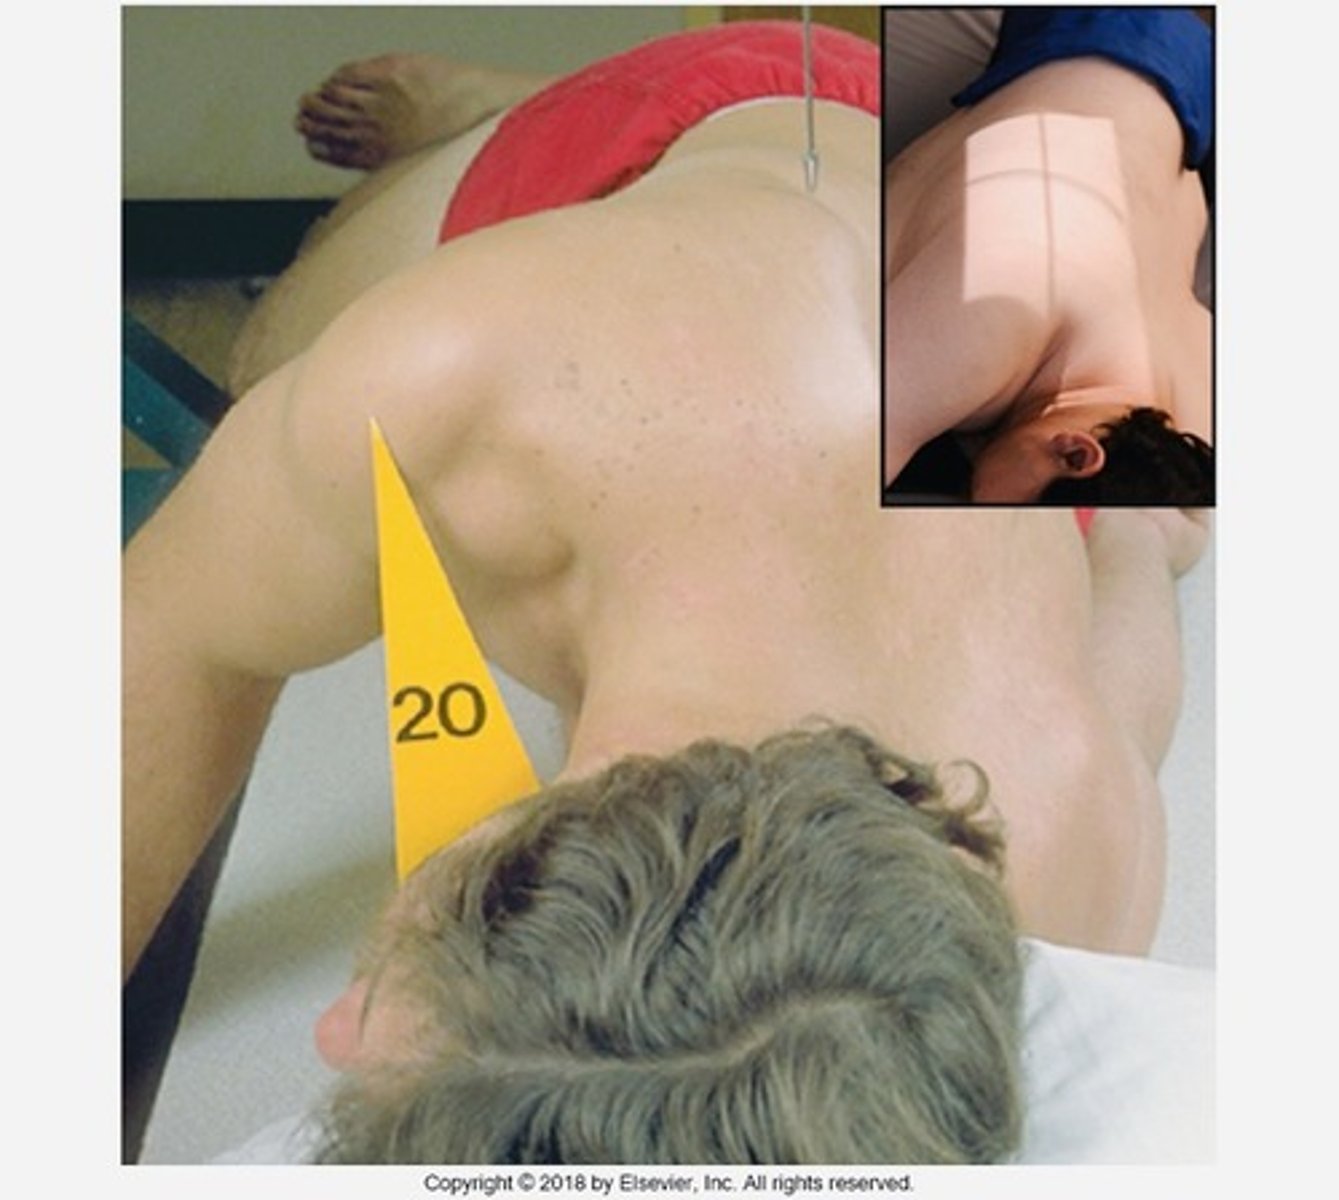

What does the Oblique T-spine demonstrate?

zygapophyseal joints

The PO Oblique T-spine demonstrates which zygapophyseal joint?

upside joint

The AO Oblique T-spine demonstrates which zygapophyseal joint?

downside joint

If the PT is in a Lateral T-spine position and you have to move them to an Oblique T-spine position, how many degrees do you oblique them?

20 degrees from lateral

If the PT is in an AP T-spine position and you have to move them to an Oblique T-spine position, how many degrees do you oblique them?

70 degrees from AP

Where do you center for Oblique T-spine?

T7